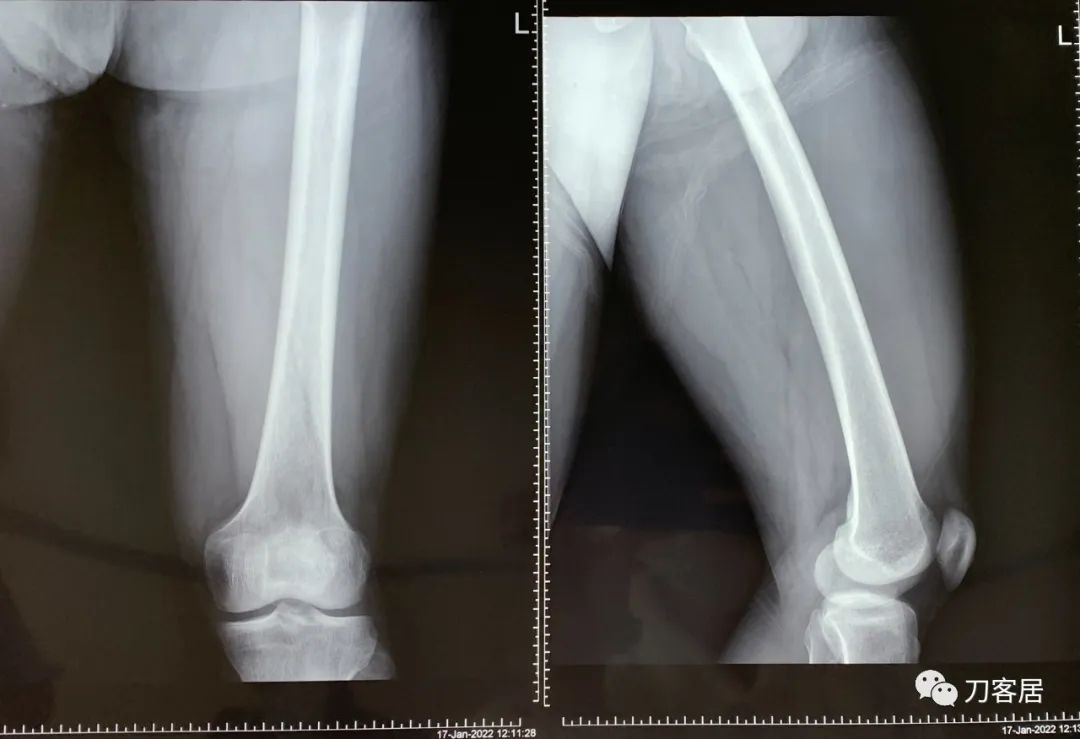

图3. 20220117宁夏医科大学总医院左股骨正侧位X线片

当地医院接诊医生给患者拍左髋关节和左股骨正侧位X线片应该是为了排除左髋关节和左股骨是否存在问题。